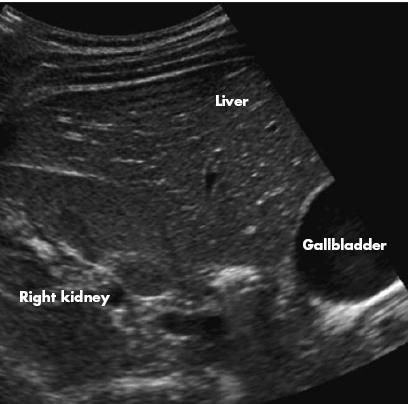

2. Based on the radiographic findings, ultrasonography of the kidneys was performed (with a peek at the gallbladder). Both the kidneys and the gallbladder were normal, without nephrolithiasis or cholelithiasis. Nevertheless, the patient still had significant right upper quadrant pain. What study would you order next?

2. Ultrasonography showed normal kidneys and gallbladder, without nephrolithiasis or cholelithiasis. What test would you order next? (A is the correct choice.)

Here the workup gets a little murky. Because the patient had right upper quadrant pain and trace hematuria, ultrasonography of the kidneys was performed in hopes that it would demonstrate the calcifications in a small adrenal gland or in the kidney-or perhaps in the gallbladder. Nephrolithiasis was thought to be less likely based on the radiographs, which demonstrate a fairly classic appearance for adrenal calcifications-an incidental finding probably resulting from a remote insult (such as a hemorrhage). However, the sonograms eliminated cholelithiasis and nephrolithiasis as possible causes of her symptoms, and we were still unable to locate the calcifications.

At this point, limited unenhanced CT of the upper abdomen was performed to characterize the calcifications once and for all.